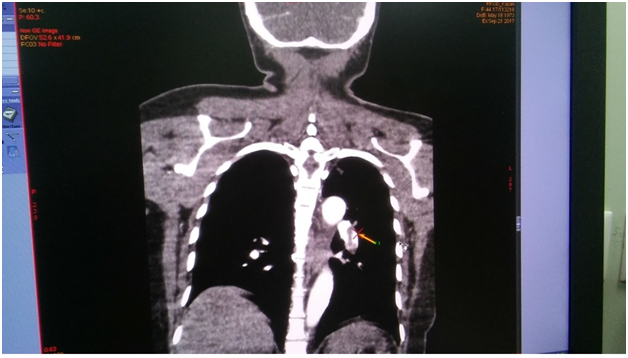

On the next day, at the day time, she felt progressive dyspnea. She was transferred to the intensive care department, where the suggestion of acute lung artery thromboembolic was taken, taken into account the character of dyspnea and extremely low level of blood saturation 60%, with weak response to oxygen therapy. The suggestion was approved by the chest tomography, where the thrombosis of both central lung arteries was revealed (Figure 1-4). After the short discussion among the colleagues, the procedure of thrombolysis was performed. We considered the extremely bad condition of the patient, weak response to oxygen therapy, young age and a kind of the operation. There were no pass to any cavity, no anastomosis, the inserted drainage system, to let blood flow out. Additionally, we had blood cell-save machine “Haemonetics Cell Saver 5+” (USA) to reinfuse blood and decrease blood loss.

Figure 3 (CT of thromboembolism in the left LA).